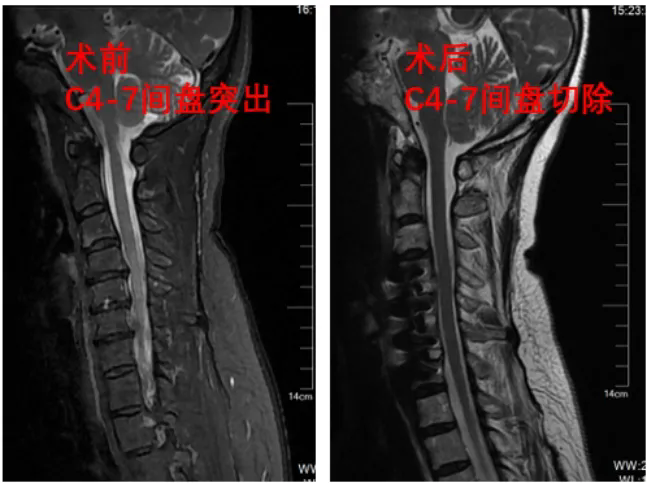

该患者长期受多节段双侧症状神经根型颈椎病困扰,经我院骨五科诊断,决定采取颈椎前路三节段颈椎间盘切除零切迹融合器植入固定手术进行治疗。该手术以往都是在肉眼直视下进行,手术切口会根据手术节段的增加进行延长,对患者的创伤也相应增加。

据骨五科副主任任伟剑介绍,为减小患者创伤,提高微创及安全性,我院在我省率先引进LUSE内镜辅助系统来辅助手术,实行三节段的颈椎减压,仅需要3厘米长度的切口(比肉眼下减压减小将近一半长度),高清内镜便可将切口内的视野进行清晰放大,还能有效减少术中气管牵拉的损伤,减压更彻底更安全,医生通过显示屏幕即可实施手术操作。

术后,患者上肢不适症状逐渐消失,经复查显示压迫症状解除。